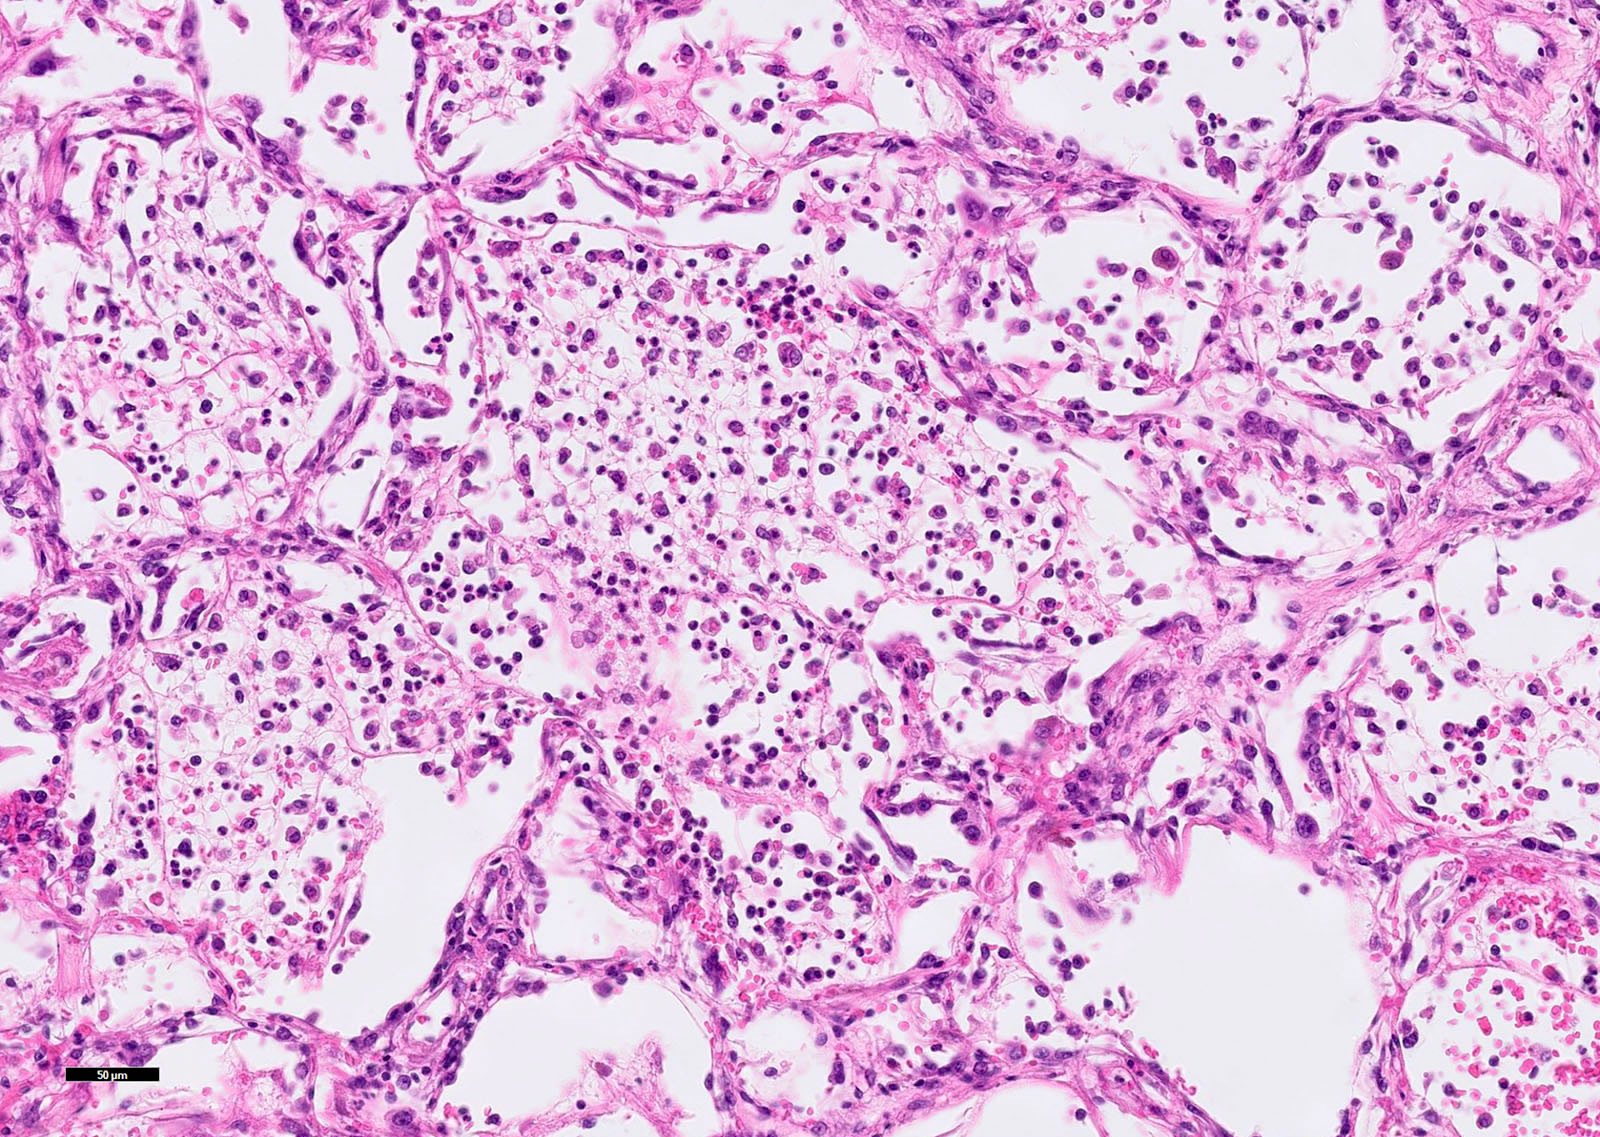

Microscopic (histologic) description

- Acute lung injury pattern:

- Diffuse alveolar damage (DAD): hyaline membrane formation

- Organizing pneumonia (OP): fibrohistiocytic proliferation with obliteration of small airways (fibroblast plug, Masson body), accompanied by inflamed surrounding alveolar interstitium

Microscopic (histologic) images

- Microscopic description

- Lungs: Sections of the lungs show intra-alveolar neutrophilic infiltrate with marked congestion. Alveolar septa are widened with mixed inflammatory cells. Reactive pneumocytes and hyaline membrane can be seen throughout the lung tissue.